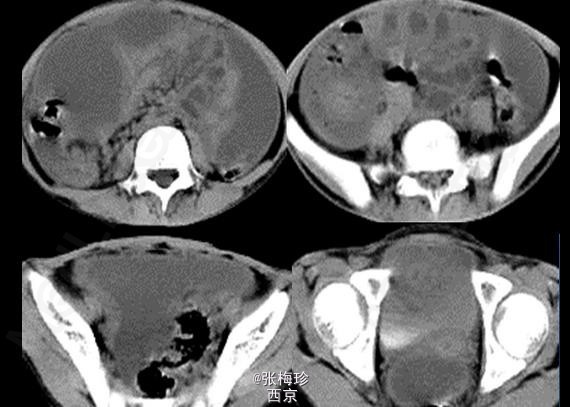

临床一例结核性腹膜炎

结核性腹膜炎

女,9岁,上腹闷痛伴腹水1年余前来就诊

查体:消瘦面容,腹膨隆,上腹部有轻压痛,无明显反跳痛,大小肿物,移动差

结核性腹膜炎 处理:药物治疗,足量、联合为治疗原则